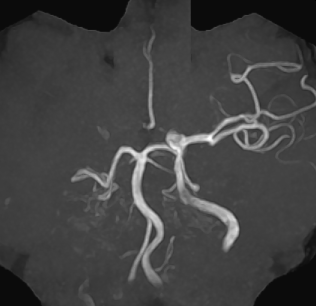

【MRA】

MRAでは左中大脳動脈が閉塞しているが、MRI,CTでの梗塞部位は血管支配領域すべてではなく、まだら状に出現。